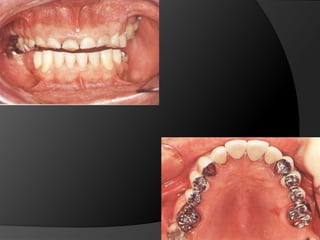

CONSIDERACIONES BIOMECÁNICAS DE LAS PRÓTESIS FIJASMolares inclinados

CORONAS DE RECUBRIMIENTO PARCIAL – Media Corona ProximalUn problema especialmente complejo es el de un molar inferior inclinado que va a ser pilar de prótesis fijaCuando el diente en perspectiva de ser pilar está inclinado hacia el espacio edéntulo, ya no es posible que su trayectoria de inserción sea a la vez paralela al eje longitudinal del diente y perpendicular al plano de oclusión

CONSIDERACIONES BIOMECÁNICAS DELAS PRÓTESIS FIJASMolares inclinados

CORONAS DE RECUBRIMIENTOPARCIAL – Media Corona ProximalUn problema especialmente complejo es el de un molar inferior inclinado que va a ser pilar de prótesis fijaCuando el diente en perspectiva de ser pilar está inclinado hacia el espacio edéntulo, ya no es posible que su trayectoria de inserción sea a la vez paralela al eje longitudinal del diente y perpendicular al plano de oclusión